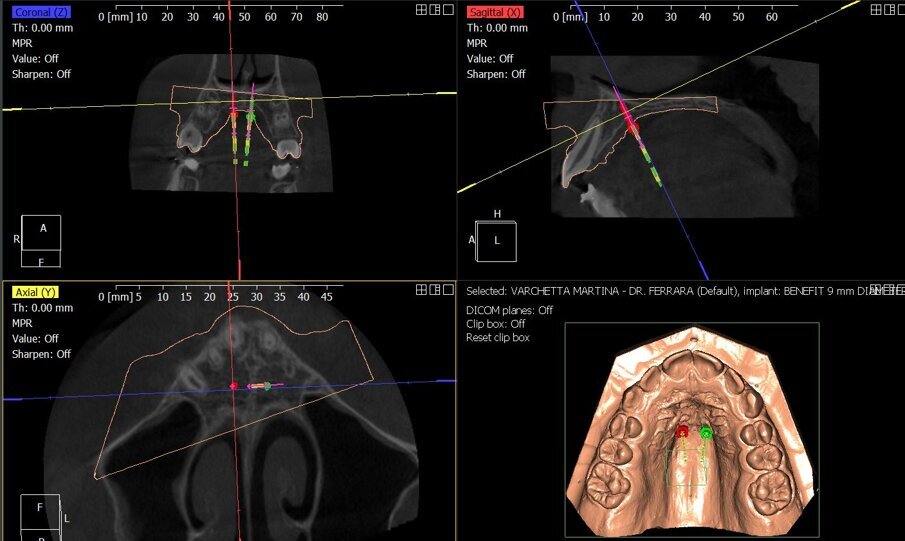

Attraverso l’esame TAC Cone Beam Computed Tomography (CBTC) è stata valutata la stadiazione della sutura palatale per scegliere la modalità di espansione più adeguata e la progettazione di dima di inserimento Computer Aided Design- Computer Aided manufacturing (CAD/CAM) si rivela strategica per determinare un posizionamento affidabile e predicibile delle miniviti ortodontiche. Questo case report mostra la correzione della discrepanza trasversale mediante un espansione con ancoraggio scheletrico mediante miniviti palatali (MARPE).

Partendo con l’acquisizione di una impronta digitale delle arcate dentarie mediante uso di scanner intraorali, o di scansione di modelli per la pianificazione del trattamento ortodontico, la metodica computer-aided design (CAD) permette la progettazione virtuale di una dima chirurgica di posizionamento per TADs basata sull’imaging della tomografia computerizzata a fascio conico (CBCT) e realizzata con computer-aided manufacturing (CAM)5, 6, 9, 10.Inoltre, tramite CBCT è possibile valutare la densità ossea e il livello di interdigitazione dei ponti ossei della sutura palatina, valutazione indispensabile per la scelta della modalità di espansione da performare.In questo case report vogliamo dimostrare come il workflow digitale abbia aiutato il clinico sia nella fase di diagnosi che nella progettazione e risoluzione della problematica ortodontica.

In questo stadio la fusione della sutura è già avvenuta parzialmente o totalmente, ed è quindi stata eseguito una MARPE. È stata progettata una dima CAD/CAM, mediante protocollo Easy Driver5. La CBCT è stata sovrapposta alla scansione digitale STL (standard triangulation language) dell’arcata dentale superiore, per valutare con estrema precisione il sito più adatto di inserimento, la lunghezza e il diametro delle viti, rispettando la profondità della volta palatina, e l’inclinazione di inserimento delle viti (Fig. 4).

Fig. 3_La CBCT permette di analizzare la morfologia della sutura palatale, in questo caso identificata con uno stadio C.

Fig. 4_Progettazione digitale mediante protocollo Easy Driver della posizione delle miniviti ortodontiche. Mediante il software è possibile programmare sito di inserimento, profondità è inclinazione dei TADs.